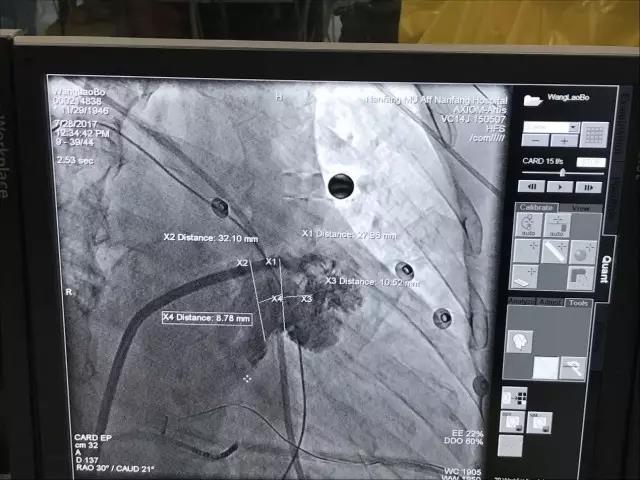

(术中DSA造影显示左心耳结构)